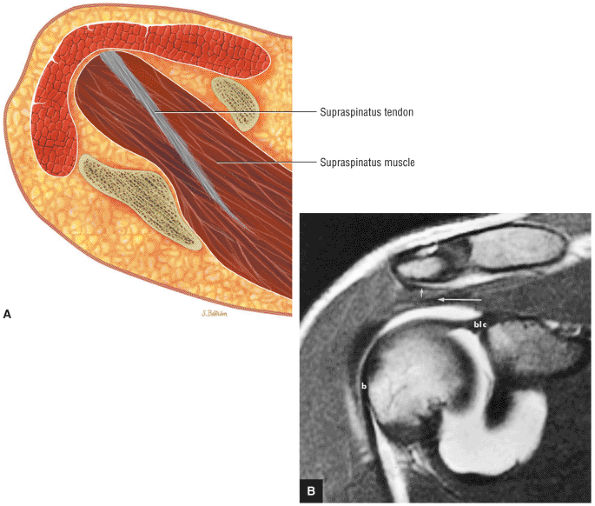

FIGURE 8.1 ● (A) Axial cross-sectional illustration showing a steeper (greater slope) obliquity of the supraspinatus tendon relative to the supraspinatus muscle. Coronal oblique MR images are correctly prescribed using image locations parallel to the supraspinatus tendon. Images improperly obtained parallel to the supraspinatus muscle and not the tendon will foreshorten the supraspinatus tendon in the coronal plane and lead to a potential misdiagnosis of a rotator cuff tear. (B) A T1-weighted coronal oblique MR arthrogram shows the continuity between the supraspinatus muscle and tendon (long white arrow), biceps labral complex (BLC), biceps tendon (b), and coracoacromial ligament (small white arrow).